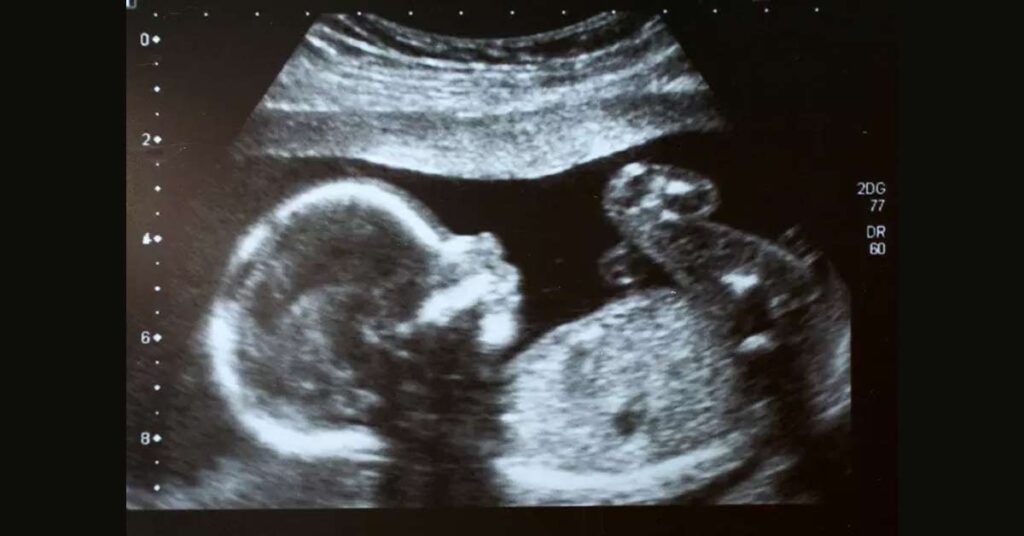

Durante a gestação, é essencial monitorar o desenvolvimento do bebê para garantir sua saúde e bem-estar. Uma das ferramentas mais úteis para os médicos é o Ultrassom, que permite estimar o peso fetal.

Este processo não só ajuda a prever possíveis complicações no parto, mas também monitora o crescimento adequado do feto ao longo dos trimestres.

Como funciona o ultrassom para estimativa de peso fetal?

O “Ultrassom” mede várias dimensões do feto, incluindo a circunferência da cabeça (CC), a circunferência abdominal (CA) e o comprimento do fêmur (CF).

Essas medidas são usadas para calcular o peso estimado do feto.